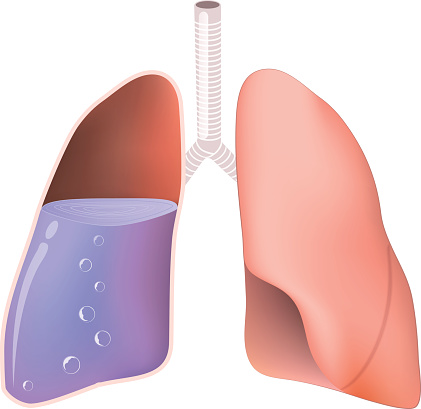

Симптомы и причины скопления воды в легких